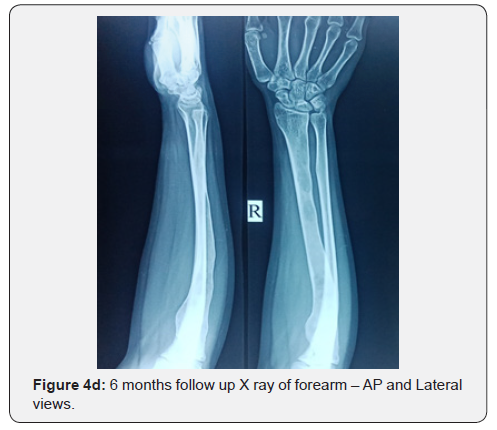

Then the patient was treated with oral risedronate 35 mg once weekly for 24 weeks, calcium and vitamin D3 combination tablets once daily for 6 months. The patient was reviewed every month with serial X rays (Figures 4a-4d) and serum calcium, phosphorus, alkaline phosphatase and vitamin D3 levels to monitor the response to treatment. The patient has been explained about the natural course, outcome and prognosis of the disease. Reassurance was given and the patient was discharged with the advice to retard heavy weight lifting and to perform daily routine activities with caution which will improve the functional quality of life.

The patient was offered with medical management with tablet risedronate 35 mg once weekly, tablet calcium aspartate 500 mg once daily and capsule vitamin D3 60,000 U once weekly for a total duration of 24 weeks. The patient was followed up every monthly interval with serial radiographs and serum calcium, phosphorus, alkaline phosphatase and vitamin D3 levels which were normalized at the end of 1 year follow up. The patient was further followed up for 1 year which show no recurrence, malignant transformation over the existing lesion, decreased intensity of pain and improved functional quality of life.